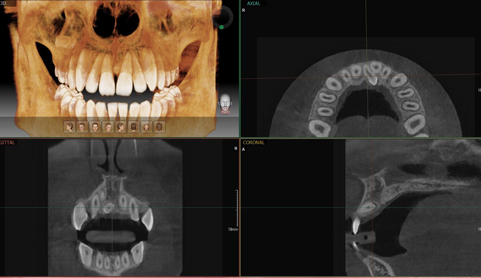

치과 3D 임플란트

보다 안전하고 확실한 임플란트 생각하면 두려운 임플란트 수술

수술 전 3D 디지털 시물레이션으로

수술 전 임플란트 위치를 잡아주는 컴퓨터 시물레이션

한치의 오차없이 정확하고 안전한 임플란트 수술이 가능합니다

네비게이션 임플란트

디지털 시뮬레이션을 통한 정확한 식립 위치와 깊이 진단.